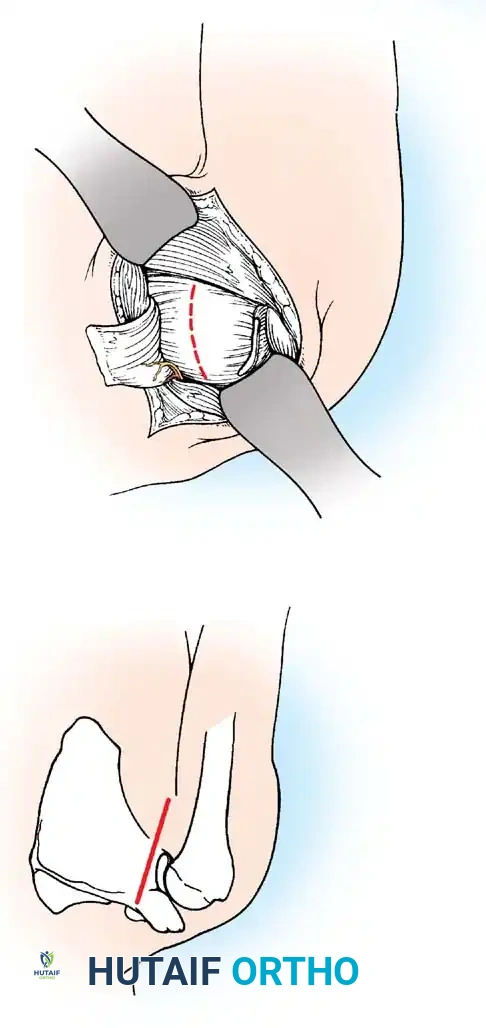

Subscapularis Management

Exposure of the anterior capsule requires navigating the subscapularis muscle. Historically, a vertical tenotomy was performed; however, modern techniques favor a subscapularis split or a peel to preserve the integrity of the muscle belly and its tendinous insertion.

- The Split: A horizontal split is made in the subscapularis at the junction of its middle and inferior thirds, extending from the lesser tuberosity medially.

- Separation: The subscapularis is carefully elevated off the underlying anterior joint capsule. This plane can be scarred in revision cases, requiring meticulous sharp dissection to avoid inadvertent capsulotomy.

Capsulotomy and Joint Inspection

A vertical or T-shaped capsulotomy is performed based on the degree of capsular laxity and the planned shift.

- For a standard Bankart repair with an inferior capsular shift, a vertical incision is made 1 cm medial to the humeral articular margin. A horizontal limb can be added to create superior and inferior capsular flaps.

Bipolar Bone Loss

A Hill-Sachs lesion is an impaction fracture of the posterolateral humeral head, created when the head is driven against the hard anterior glenoid rim during dislocation. Burkhart and DeBeer introduced the concept of the "engaging" Hill-Sachs lesion, which levers the humeral head out of the joint when the arm is abducted and externally rotated.

Concurrently, anterior glenoid rim fractures or attritional bone loss can occur. Itoi demonstrated that a 20% loss of the anterior glenoid width critically compromises stability, rendering soft-tissue repairs (like an isolated Bankart repair) biomechanically insufficient. Advanced imaging (3D CT or MRI arthrography) is mandatory to quantify bone loss.